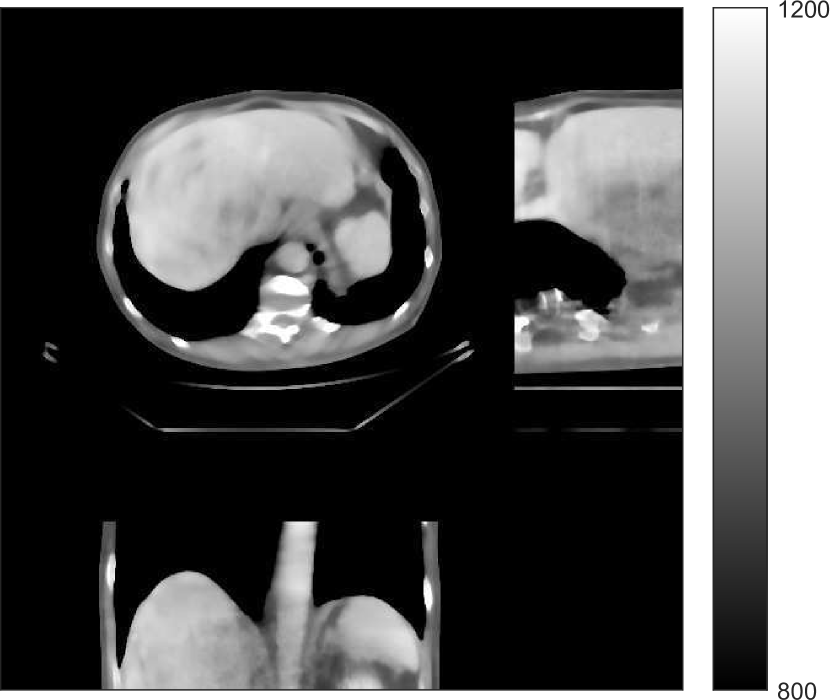

V-B2 Reconstruction results for the synthesized clinical data

Fig. 9 shows three axial slices from the 3D reconstructions with SPULTRA and PWLS-ULTRA at : the middle slice (No. 67) and two slices located farther away from the center (No. 90 and No. 120). The image profiles along a horizontal line (shown in green) in the displayed slices are also shown in Fig. 9. The reconstructed slices using PWLS-ULTRA appear darker around the center compared to the “true” clinical image and the reconstructions with SPULTRA. This means PWLS-ULTRA produces a strong bias in the reconstruction. The bias can be observed more clearly in the profile plots: the pixel intensities for the SPULTRA reconstruction better follow those of the “true” clinical image, while those for the PWLS-ULTRA reconstruction are much worse than the “true” values. Moreover, SPULTRA achieves sharper rising and failing edges compared to PWLS-ULTRA. In other words, SPULTRA also achieves better resolution than PWLS-ULTRA. Fig. 9 also shows a zoomed-in ROI for each of the chosen slices, and highlights some small details with arrows. It is clear that in addition to reducing the bias, SPULTRA reconstructs image details better than PWLS-ULTRA.